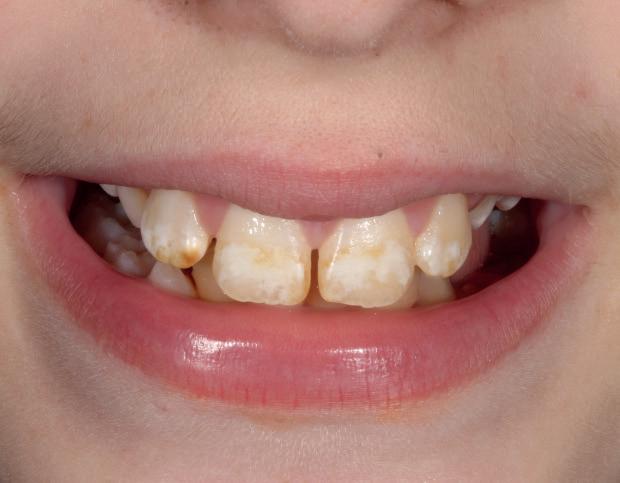

material matters

To use clear aligners to their greatest potential, it’s important to look briefly at their treatment ceiling. Complex cases that include severe bite issues, large gaps, or severe crowding may make this form of treatment less suitable, instead requiring traditional fixed braces. The literature has also cited distalisation, rotation and extrusion as some of the more difficult movements to carry out successfully with clear aligners, and whilst it is not impossible to achieve these results, a relevant case may prompt the need for an alternative treatment approach.

However, recent developments in the materials used to create clear aligners as well as clinical approaches have improved predictability in a wider range of cases.

Polyethylene terephthalate glycol (PETG) materials have been the solution of choice for many complex designs due to their durability, high impact strength and resistance to chemical changes. With impressive mechanical and optical properties, it’s easy to see why they are increasingly preferred.

The future of complex clear aligner cases could lie in shape memory polymers (SMPs), sometimes known as actively moving polymers. This material offers the ability to revert to an original shape when achieving a necessary transitionary trigger, such as a certain temperature for a designated time period. During a treatment cycle, the SMP-based aligner could be subjected to such a trigger, reverting to a predefined shape, and in turn generating forces which can produce orthodontic tooth movement. When designed to harbour multiple aligner shapes within its form, it could reduce the number of aligners used during orthodontic treatment and achieve complex corrections sooner.

Step by step

When tackling a complex case suitable for aligner therapy, treatment is most effective when the dentist creates an efficient and actionable treatment plan. Therefore, one of the most important skills for a clinician providing clear aligners for complex cases is an understanding of how to implement staging.

Those that have prior experience in orthodontics may know that staging refers to the breakdown of an intended movement of teeth in a sequential manner, with the use of aligners. This segmented approach

allows for the close control over linear and rotational movements over time, with each new aligner achieving a specific step that gets a patient closer to their end goal. In complex cases, staging orthodontic tooth movement is essential and can be used to attain better treatment outcomes.

When used in the treatment of severe crowding, staging has provided no significant differences in results when compared to fixed brace treatments, including in case duration. One 2022 study broke up the process into three overarching stages of ‘decrowding‘, ‘space closure’ and ‘fine-tuning’. This allows for targeted movement of the crowded anterior teeth, before achieving a class I canine and molar relationship, and making final adjustments, such as overcorrections – recommended by many in case of possible relapses – and closures of any residual spaces.